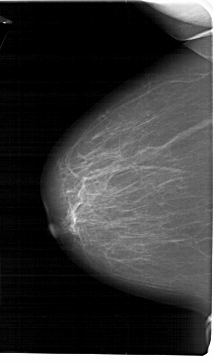

A_1729_1.LEFT_CC

LEFT_CC LINES 6871 PIXELS_PER_LINE 4066 BITS_PER_PIXEL 12 RESOLUTION 43.5 NON_OVERLAY